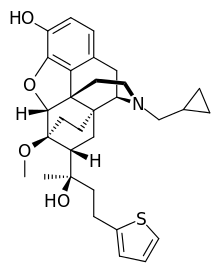

The pharmacodynamic response to an opioid depends upon the receptor to which it binds, its affinity for that receptor, and whether the opioid is an agonist or an antagonist. For example, the supraspinal analgesic properties of the opioid agonist morphine are mediated by activation of the μ1 receptor; respiratory depression and physical dependence by the μ2 receptor; and sedation and spinal analgesia by the κ receptor. Each group of opioid receptors elicits a distinct set of neurological responses, with the receptor subtypes (such as μ1 and μ2 for example) providing even more [measurably] specific responses. Unique to each opioid is its distinct binding affinity to the various classes of opioid receptors (e.g. the μ, κ, and δ opioid receptors are activated at different magnitudes according to the specific receptor binding affinities of the opioid). For example, the opiate alkaloid morphine exhibits high-affinity binding to the μ-opioid receptor, while ketazocine exhibits high affinity to ĸ receptors. It is this combinatorial mechanism that allows for such a wide class of opioids and molecular designs to exist, each with its own unique effect profile. Their individual molecular structure is also responsible for their different duration of action, whereby metabolic breakdown (such as N-dealkylation) is responsible for opioid metabolism.

A new strategy of drug development takes receptor signal transduction into consideration. This strategy strives to increase the activation of desirable signalling pathways while reducing the impact on undesirable pathways. This differential strategy has been given several names, including functional selectivity and biased agonism. The first opioid that was intentionally designed as a biased agonist and placed into clinical evaluation is the drug oliceridine. It displays analgesic activity and reduced adverse effects.[162]

Several semi-synthetic opioids were developed in Germany in the 1910s. The first, oxymorphone, was synthesized from thebaine, an opioid alkaloid in opium poppies, in 1914.[228] Next, Martin Freund and Edmund Speyer developed oxycodone, also from thebaine, at the University of Frankfurt in 1916.[229] In 1920, hydrocodone was prepared by Carl Mannich and Helene Löwenheim, deriving it from codeine. In 1924, hydromorphone was synthesized by adding hydrogen to morphine. Etorphine was synthesized in 1960, from the oripavine in opium poppy straw. Buprenorphine was discovered in 1972.[228]